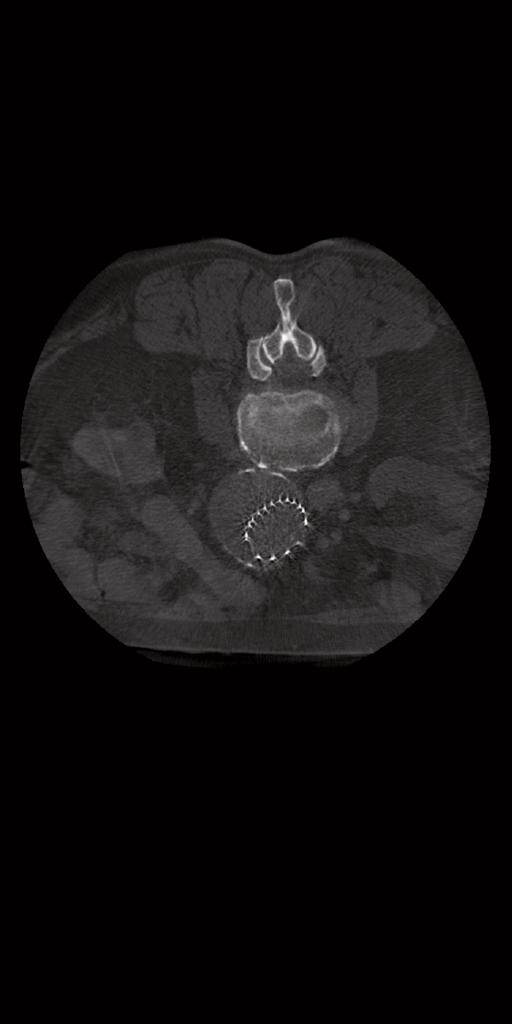

syngo DynaCT avec

visualisation des vaisseaux nourriciers d’une tumeur hépatique à un stade

précoce. Avec l’autorisation de l’hôpital universitaire de Tübingen, Allemagne

Les systèmes ARTIS icono s’accompagnent d'outils de guidage intelligent comme syngo Embolization Guidance, qui vous assiste dans l’identification semi-automatique des vaisseaux nourriciers et la navigation anatomique, par exemple lors du traitement des tumeurs hépatiques (TAE, TACE, SIRT) ou d’une hyperplasie bénigne de la prostate (PAE).

La détection semi-automatique des vaisseaux nourriciers est réalisable pour les données acquises avec syngo DynaCT ou MDCT injectés.

Pour en savoir plus sur syngo Embolization

Guidance, cliquez à droite.

Avec l’autorisation de l’hôpital universitaire de Tübingen, Allemagne